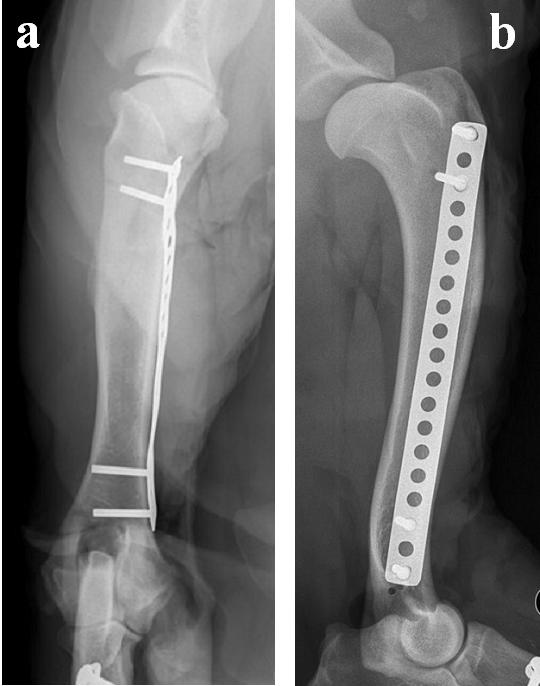

Validarea poziționării corecte a plăcii în raport cu osul și a selecției adecvate a dimensiunii și numărului șuruburilor s-a realizat prin examen imagistic radiografic convențional, utilizând incidențele clasice, respectiv incidența medio-laterală și incidența cranio-cau -

Figura 12. Punctele de reper și poziția câinelui pe masa de operație pentru abordul minim invaziv al femurului - a)Trocanterul mare al femurului. b) Condilul lateral al femurului. c) Patela. d) Poziția femurului și orientarea lui pe masa de operație

dală (figura 17). Aceste investigații au relevat că spațiile articulare proximal (acetabul - cap femural) și distal (condilii femurali lateral și medial - platou tibial) au rămas nemodificate. Patela și oasele sesamoidiene au rămas integre și nu s-au înregistrat modificări ale poziției acestora.

Figura 17. Imaginea radiografică a coapsei după fixarea plăcii – incidență cranio-caudală (a) și medio-laterală (b).